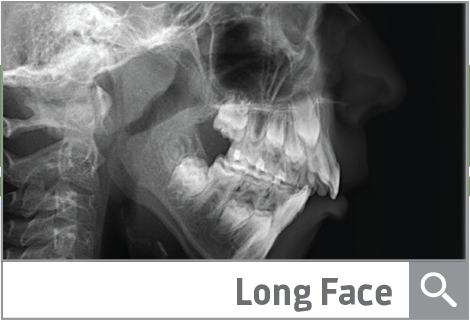

Long Face Syndrome With Thumb Sucking Habit

A young patient with a thumb sucking habit and severe skeletal open bite leads this Townie to mixed feelings on how to treatment plan.